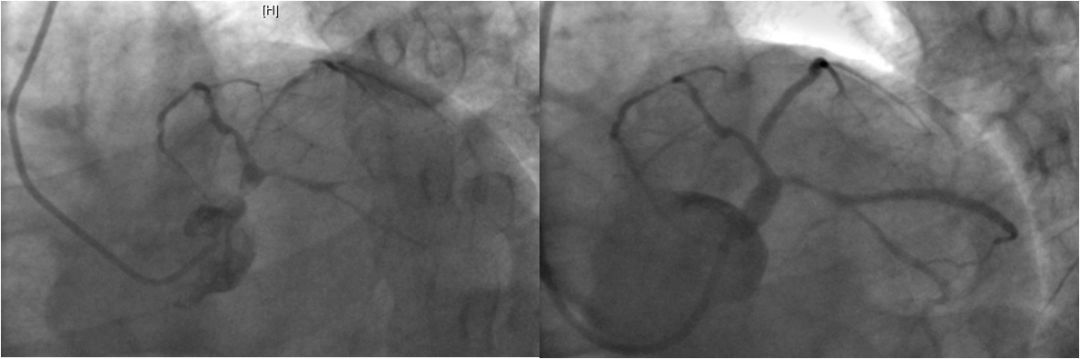

LM狭窄约50%,LAD近段完全闭塞,LCX中远段弥漫性病变,最重90%以上,RCA粗大,全程可见粥样硬化斑块。与家属沟通后拟对LAD行PCI术,EBU3.5/GC至左冠开口,Runthrough导引导丝通过LAD近段闭塞病变部位至远端,抽吸导管反复抽吸近段,再造影见远段显影,2.5*20mm球囊以8atm压力扩张病变部位,于病变部位植入3.0*21mm涂层支架一枚。术中顺利,冠脉内推注欣维宁10ml